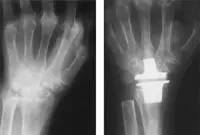

X线:移植前的腕部严重类风湿关节炎(左)腕关节硅胶植入物置换术后(右)